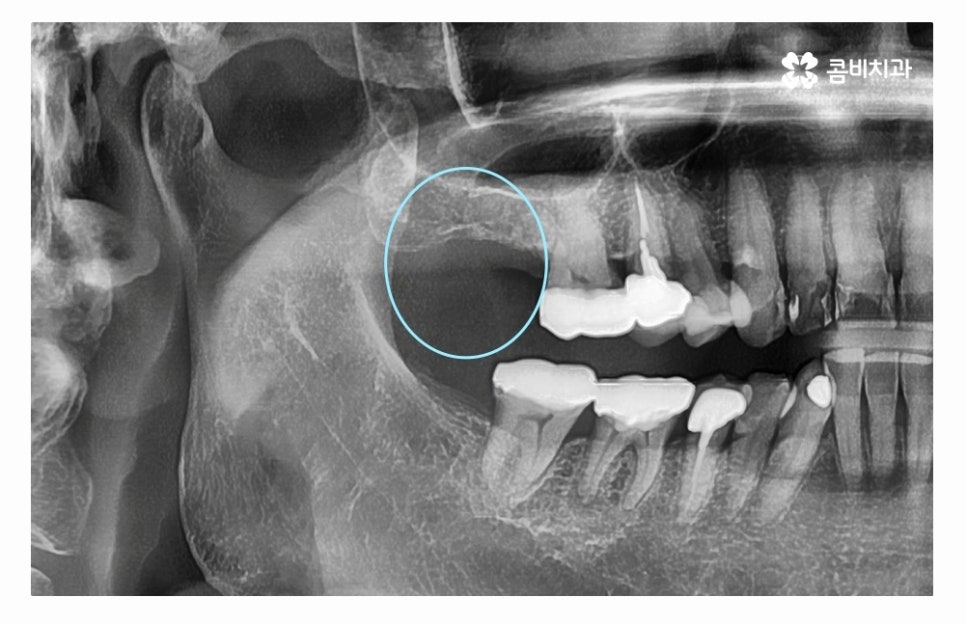

임플란트수술의 원리는 잇몸 뼈에 인공 치근을 식립하고

지대주로 단단하게 고정력을 얻은 후에 보철물을 연결하여

치료를 마무리하게 되는데 자연치아도 그렇듯이

임플란트 역시도 잇몸 뼈의 상태가 매우 중요하다고 할 수 있는데요.

치아를 잃게 되었을 때 곧바로 임플란트 수술을 해야 하는 이유도

임플란트를 건강하게 치료하기 위해서는 잇몸 상태가 중요한데

치아를 잃고 그대로 방치하면 잇몸이 점점 흡수되기 때문이라고 할 수 있어요.